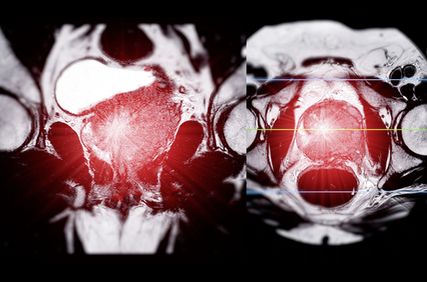

Therapiestrategien beim hormonsensitiven Prostatakarzinom

Die Therapielandschaft des fortgeschrittenen Prostatakarzinoms hat sich seit 2014 und damit der ersten Präsentation der CHAARTED-Studie praktisch jährlich verändert und erweitert. Heute stehen sehr viele und wirksame Therapieoptionen zur Verfügung.